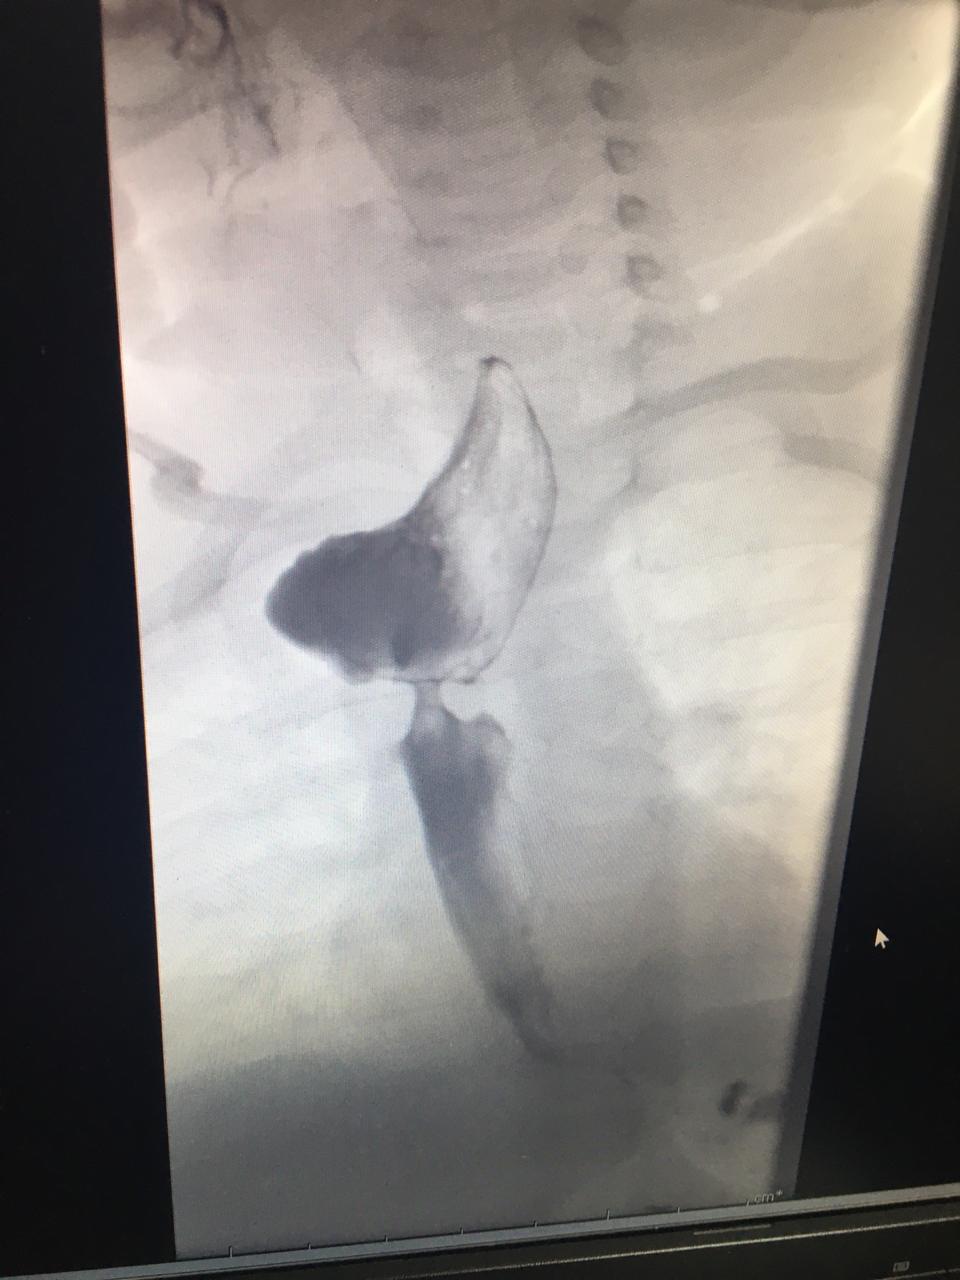

أحداث اليوم - أُجري مؤخراً في مستشفى الجامعة الأردنية عمليّة تنظير نوعيّة لطفلة تعاني من انسداد تام في المريء تم خلالها عمل توسعة له باستخدام البالون والأشعّة التداخُليّة (X-Ray guided wire) وفق أعلى معايير السلامة والأمان، قام بها الدكتور فريد خضير استشاري الجهاز الهضمي والكبد والتغذية للأطفال في المستشفى يُسانده فريق طبي ضم كل من استشاري التخدير الأستاذ الدكتور صبحي الغانم واستشاري جراحة الأطفال الدكتور رائد الطاهر بالإضافة إلى تمريض وحدة التنظير والعمليات.

وقال الدكتور خضير عضو هيئة التدريس في كلية الطب في الجامعة الأردنية بأنّ الطفلة والتي تزن (4) كيلو غرام عند تحويلها إلى المستشفى كانت تعاني من انسداد تام في المريء تشكّل بعد إجرائها لعملية جراحيّة فيه بسبب وجود تشوّه خلقي (Esophageal atresia)، مما أدى إلى تلقي التغذية حينها عن طريق فتحة جراحيّة في البطن نحو المعدة مباشرة (Feeding gastrostomy) مع وجود مشاكل في بلع اللعاب الأمر الذي كان يؤدّي إلى ارتداده إلى الرئتين بشكل دائم بالإضافة إلى احتياجها إلى جهاز تنفس في البيت (CPAP).

وبين الدكتور خضير بأن المريضة كانت قد خضعت لأولى جلسات التنظير خلال شهر رمضان المبارك في عمليّة امتدّت لحوالي ساعتين تم خلالها عمل توسعة للمريء باستخدام جهاز تنظير المعدة للأطفال والدخول إلى المعدة من خلال فتحة التغذية الموجودة على بطن الطفلة ومن ثم تم عمل توسعة للمريء باستخدام البالون (retrograde balloon dilation)، وقد خضعت في وقتٍ لاحق لجلسات تنظير بهدف متابعة تضيّق المريء والعمل على توسعته بشكل أفضل.